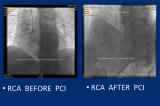

Աջ կորոնար զարկերակի (RCA) ռեվասկուլյարիզացիա և ստենտավորում «Stent for life» ՀՀ պետծրագրի շրջանակում

Տղամարդ` 59 տարեկան, ռիսկի գործոններ. ճարպակալում զարկերակային հիպերտենզիա...

Նույն օրը` ապրիլի 19-ին իրականացվել է սելեկտիվ ռեկորոնարոգրաֆիա: Արդյունքում հայտնաբերվել է, որ կորոնար անոթավորումն աջ դոմինանտ տիպի է, ձախ առաջային վայրէջ կորոնար զարկերակը (LAD) աթերոսկլերոտիկ ախտահարված է, մոտակա-միջին հատվածում վաղ իմպլանտացված ոչ դեղապատ ստենտը տոտալ խցանված է ՝100% թրոմբոտիկ զանգվածի առկայությամբ: Գոտևորող կորոնար զարկերակը (CX)-աթերոսկլերոտիկ ախտահարված է՝ առանց տեսանելի նեղացումների, աջ կորոնար զարկերակը (RCA) աթերոսկլերոտիկ ախտահարված է՝ առանց տեսանելի նեղացումների:

Արդյունքում վերականգնվել է արյան անտեգրատ հոսքը (TIMI III):